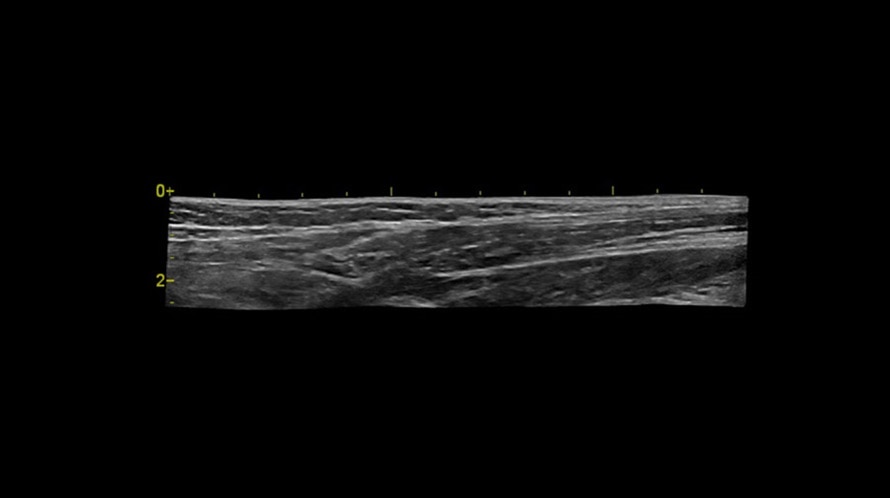

Auto IMT

Обеспечивает автоматическое определение границ и толщины комплекса интима-медиа и выполнение требуемых измерений.